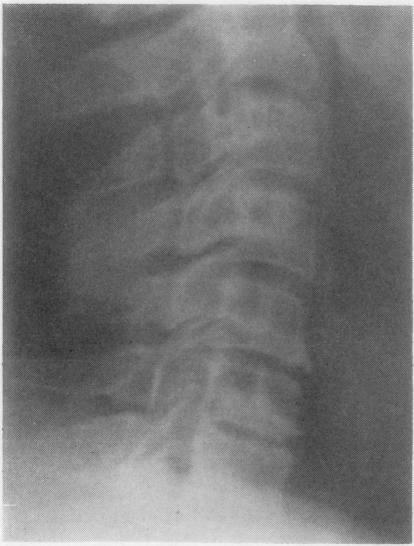

Radiological changes in the sacro-iliac joints and spine of patients with psoriatic arthritis and psoriasis.

Ann Rheum Dis. 1968 Jan;27(1):1-6. doi: 10.1136/ard.27.1.1.